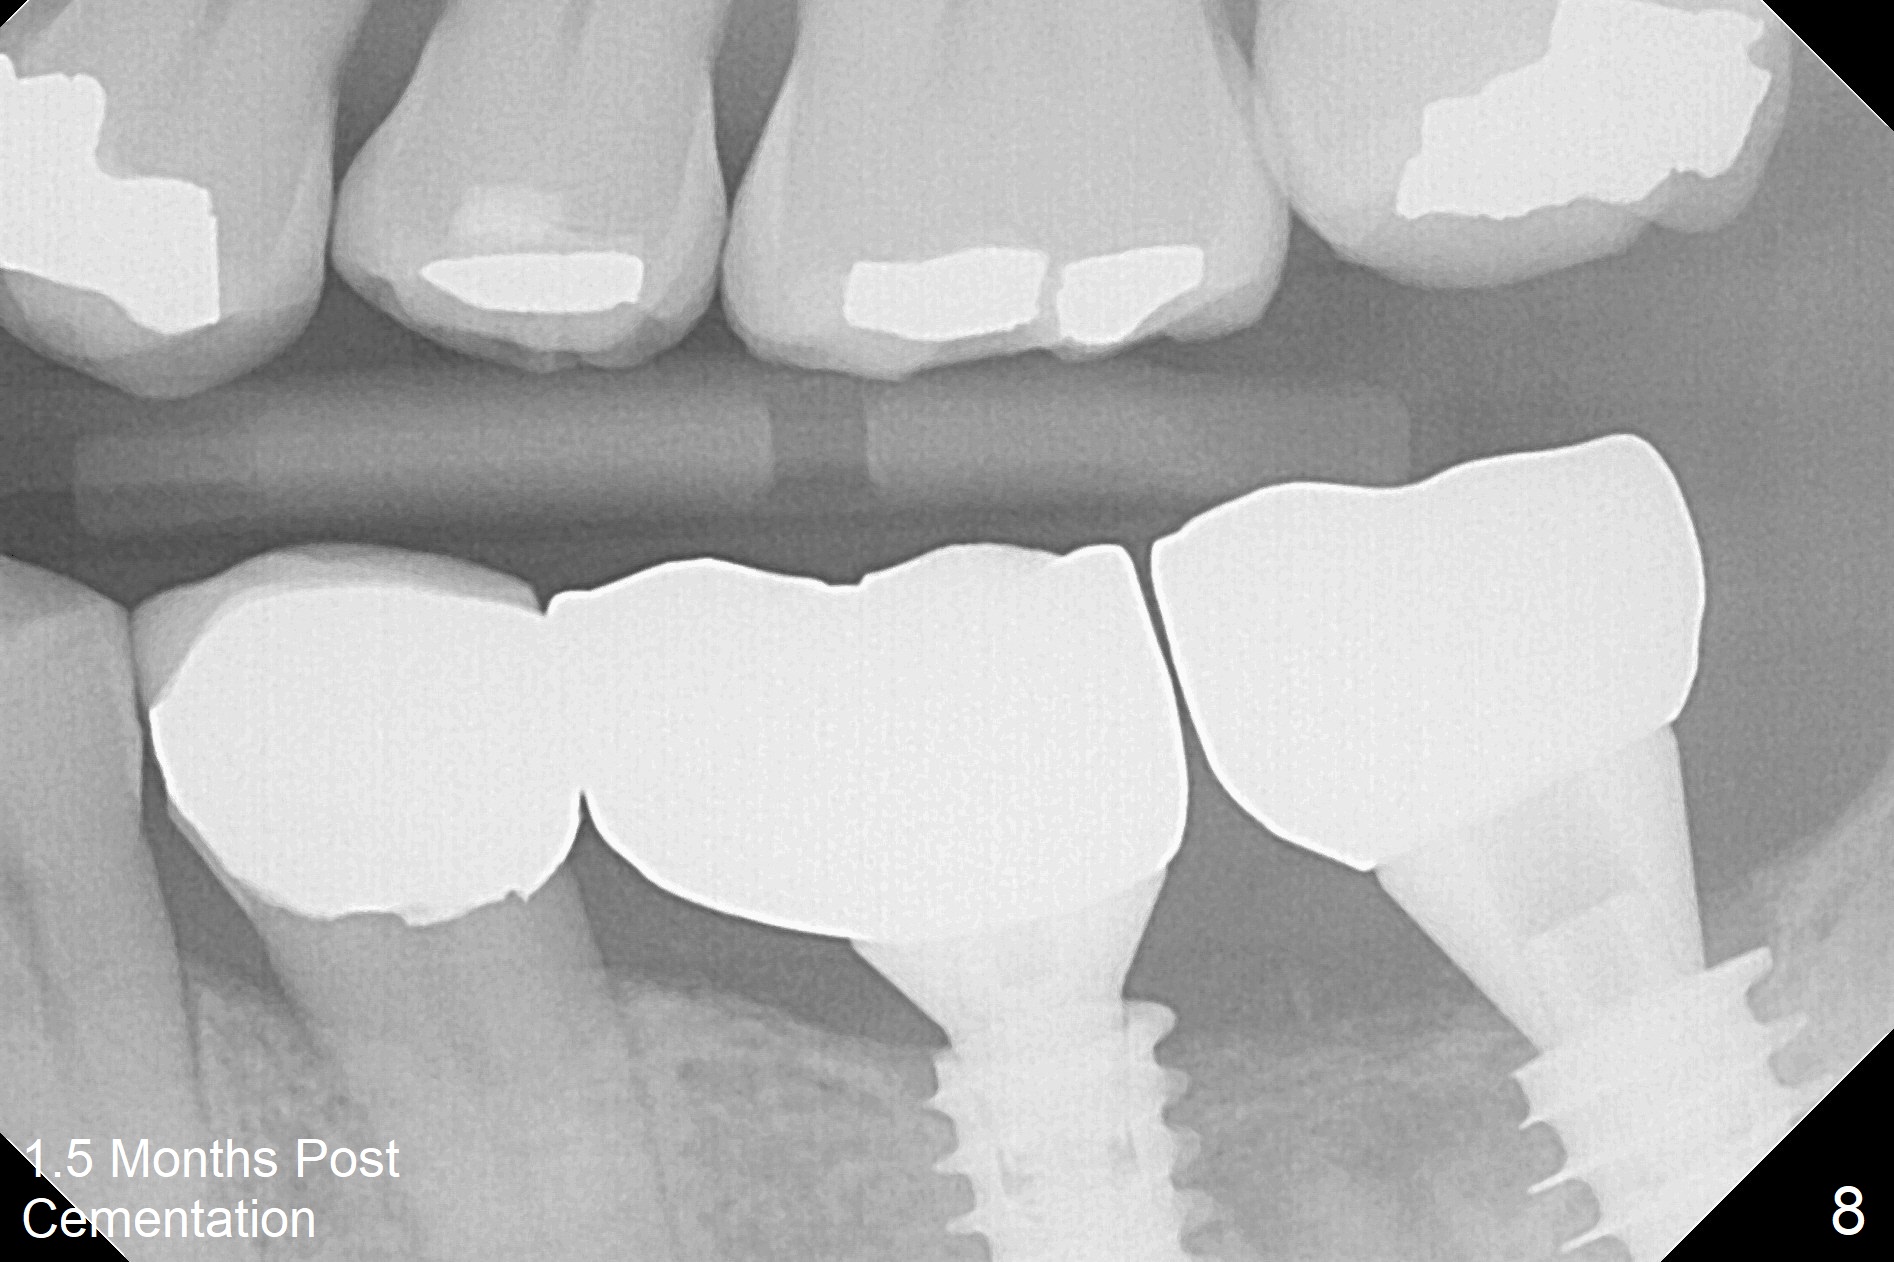

A drawback of placing an implant in the distal socket of the 2nd lower molar is closer to the Inferior Alveolar Canal.  The implants seem to have osteointegrated 4.5 months postop (Fig.5).  While the ridge at #19 appears to be wider than preop (as compared to Fig.1), that at #18 seems to be atrophic 5 months postop (Fig.6 * (1 week post cementation)).  The distal implant placement at #19 may increase possibility of abutment screw loosening during functioning (Fig.7 *).  When the patient returns for periodic exam 1.5 months post cementation, loose contact between the implant crowns is noted (Fig.8).  The bony trabeculae form between the 2 implants crestally 12 months postop, i.e., 7 months post cementation (Fig.9).  The loose contact between the 2 implants is corrected 14 months post cementation.